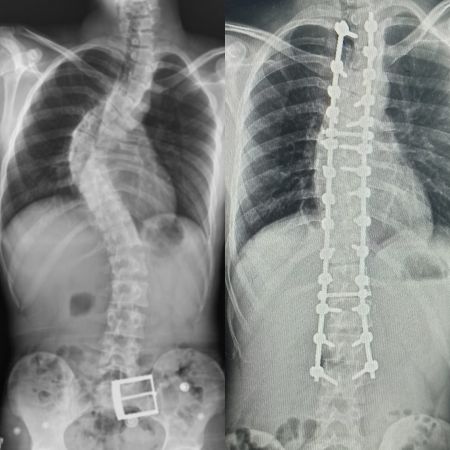

Yapılan muayene ve incelemeler sonucu hastada 73 derece skolyoz (omurga eğriliği) ve kifoz (kamburluk) tespit edilerek Ahmet Akan’a ameliyat önerildi. Samsun Üniversitesi Tıp Fakültesi Ortopedi ve Travmatoloji Anabilim Dalı Öğretim Üyelerinden Dr. Öğr. Üyesi Ömer Bozduman, deneyimli ameliyat ve anestezi ekibi eşliğinde görev yaptığı Samsun Eğitim ve Araştırma Hastanesi’nde 7 saat süren başarılı bir skolyoz ameliyatı gerçekleştirdi.

Hasta ile ilgili bilgi veren Dr. Öğretim Üyesi Ömer Bozduman, “Hastamız artan sırt ağrıları ve omurga eğriliğinin ilerlemesi şikâyetiyle kliniğimize başvurdu. İnceleme ve değerlendirmelerimiz sonucu ameliyat kararı verdik. 7 saat süren skolyoz ameliyatını takiben 12 saat sonra hastamız kaldırılıp yürütüldü. Ameliyat sonrası nörolojik olarak hiçbir sorunu yok. Eğriliği tamamen düzeldi, boyu uzadı. Şu an kendisi yürüyüp gezebiliyor. Hastayı 5 gün sonra taburcu edip evine gönderiyoruz. Her ameliyatta olduğu gibi skolyoz ameliyatlarında da ekip çalışması çok önemlidir. Uzun süren bu ameliyatı, hastanemizin özverili ameliyat ve servis hemşireleri ve deneyimli anestezi ekibi ile gerçekleştirdik” dedi.